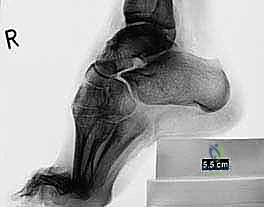

الشكل 2 • تشوهات القدم الجوفاء، منظر أمامي. يوضح مكونات انقلاب الكعب للداخل وتقوس مقدمة القدم، مما يؤدي إلى عدم استقرار الكاحل.